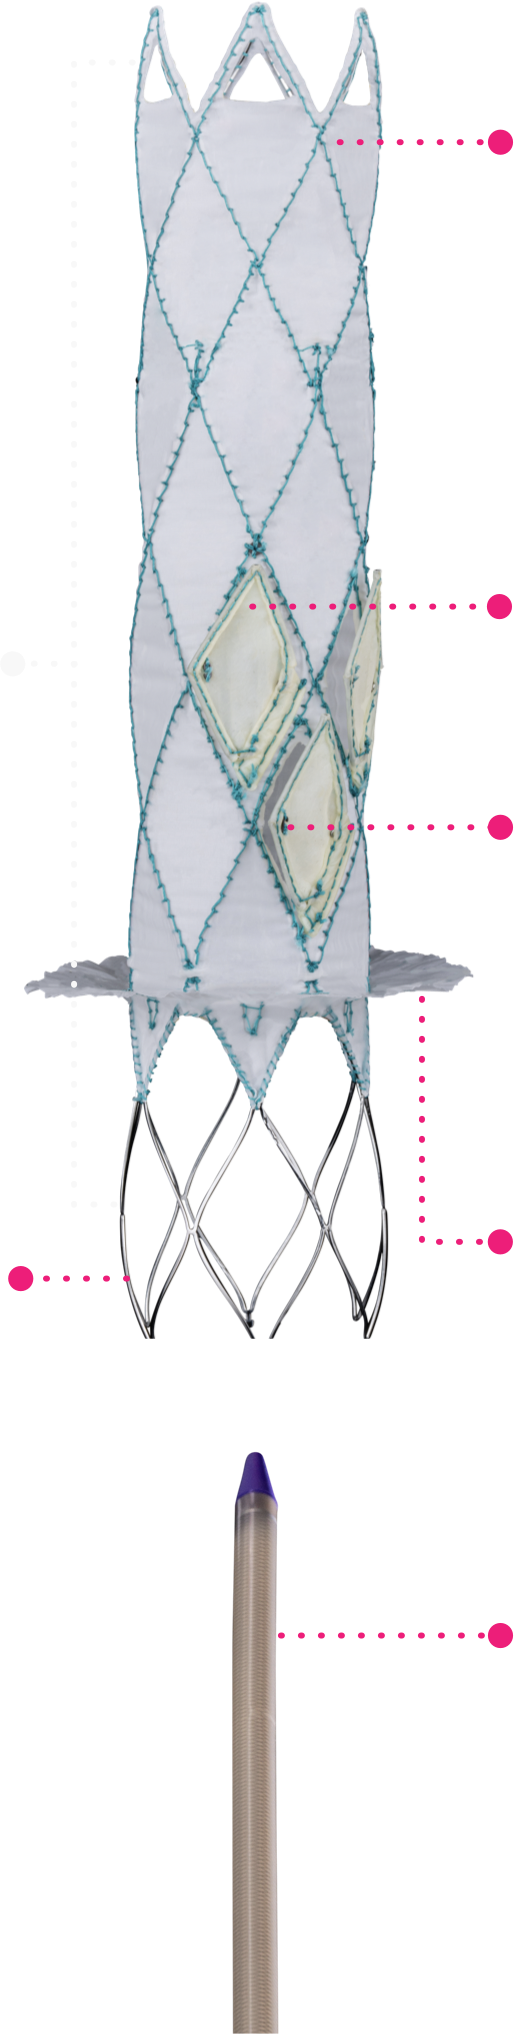

Technical Excellence for Comprehensive Care

Trillium™ is meticulously crafted for the unique demands of the tricuspid valve environment.

This stent graft, featuring a valved wall, is designed to span the right atrium with secure fixation

in the Superior Vena Cava (SVC) and Inferior Vena Cava (IVC), leaving the native valve untouched.

Migration Resistant

A single device anchored to two

apposing anatomies (SVC & IVC),

provides reliable anchoring and full

migration resistance.

Multiple, Normally Open Valves

Provide extremely low filling

(diastolic) pressures, with an

increased closing volume for the

benefit of patients with RV failure.

Large Flange Sealing Skirt

Creates a secure seal that fits a wide

range of anatomies, while allowing

the necessary hepatic vein inflow.

Mechanically Durable

Designed for long-term fatigue

resistance. Durable for decades of

cardiac function.

Radio-Opaque Markers

Ensure precise positioning under a

strictly fluoroscopic procedure.

Atraumatic Stent Ends

Provides reliable anchoring,

reducing the risk of complications

during and after the procedure.

Low Profile Delivery System

24 Fr delivery system for

venous transfemoral approach.